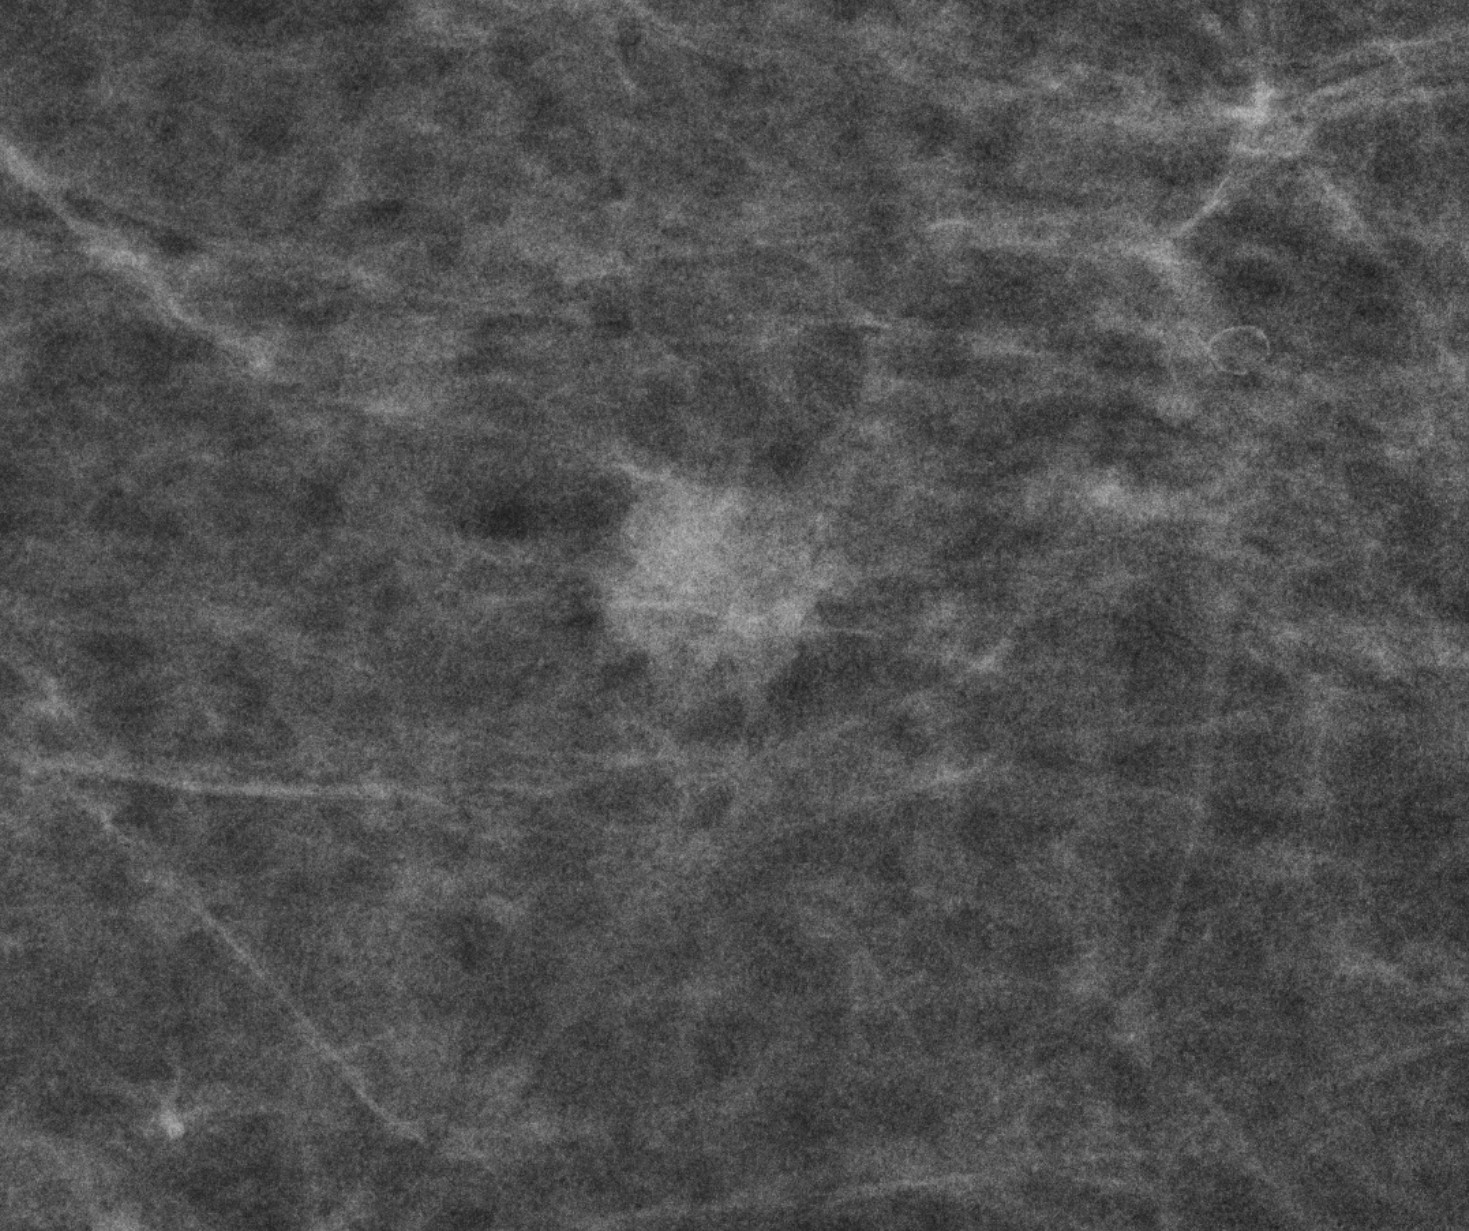

Mammografie-Screening-Programm: Brustkrebssterblichkeit könnte weiter gesenkt werden

Die in Berlin vorgestellte „Evaluation der Brustkrebsmortalität im deutschen Mammografie-Screening-Programm" zeigt, dass dieses weltweit größte Früherkennungsangebot die brustkrebsbedingten Todesfälle bundesweit signifikant im Vergleich zu nicht teilnehmenden Frauen verringert hat. Doch es könnten viel mehr Menschen profitieren.

Berlin, im Juli 2025 ¬– Die Deutsche Gesellschaft für Senologie (DGS) begrüßt ausdrücklich die jetzt vorgestellten Studienergebnisse1 zur Wirksamkeit des Mammographie-Screening-Programms2. Die wissenschaftliche Auswertung zeigt eindrucksvoll, dass die Teilnahme am Screening die Brustkrebssterblichkeit um 20 bis 30 Prozent senkt. Damit wird bestätigt, was die Wissenschaft seit Jahren beobachtet – Brustkrebsfrüherkennung rettet Leben.

Besonders hervorzuheben ist die Qualität des deutschen Programms, das mit rund 14 Millionen anspruchsberechtigten Frauen weltweit führend ist. Die Studienergebnisse unterstreichen, dass der Nutzen der Untersuchung den potenziellen Risiken deutlich überwiegt – ein zentrales Kriterium für jede Früherkennungsmaßnahme. De facto nutzen jedoch nur etwa die Hälfte der anspruchsberechtigten Frauen zwischen 50 und 75 Jahren dieses wichtige Vorsorgeangebot. Bundesgesundheitsministerin Nina Warken appellierte in Berlin, verstärkt von dieser Chance Gebrauch zu machen.